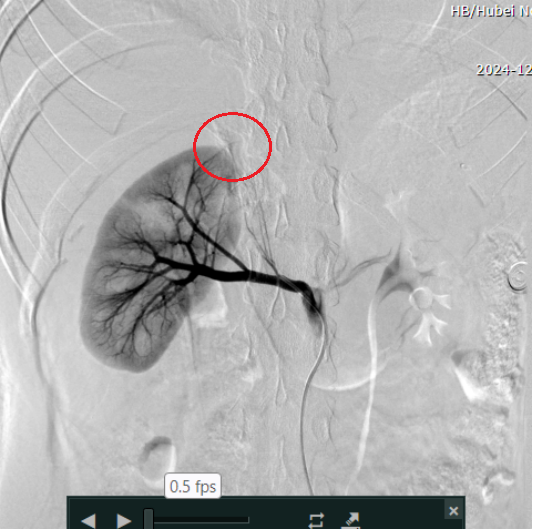

占必兴立即联系放射科主任刘良进,二人争分夺秒,就如何既能迅速止血救命、又能保住患者肾脏紧急讨论,最终制定了创新介入手术方案——超选择性肾动脉栓塞术。通过微小的导管直达肾脏受损血管,精准栓塞出血点,既有效控制出血,又最大限度保留肾脏功能。

术后

方案一经确定,手术立即启动。介入室内,泌尿外科团队与放射科介入团队密切配合,凭借丰富的经验和精湛的技术有条不紊地置入导管、精准定位、栓塞……手术圆满完成,年轻患者珍贵的肾脏得以保全。当医护人员把结果告诉患者奶奶时,年迈的奶奶再次流下眼泪。

复查显示,小林的右肾功能正在逐步恢复,这无疑是对医护人员日夜守护、精心治疗的极大鼓舞与肯定。